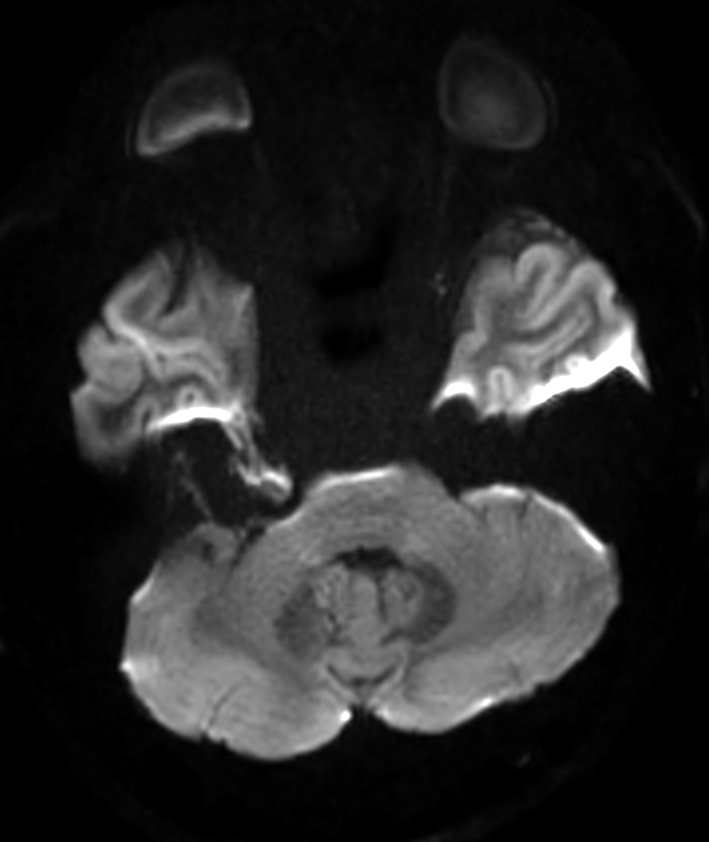

Patient with an IAC lesion. Comparing different DWI methods (EPI, TSE, ZOOM). Compressed SENSE is added to all TSE sequences to decrease scan times, thereby shortening the time the patient has to spent in the magnet. The dS Head 32ch coil is used to enhance image quality.

DWI EPI ZOOM (b1000)